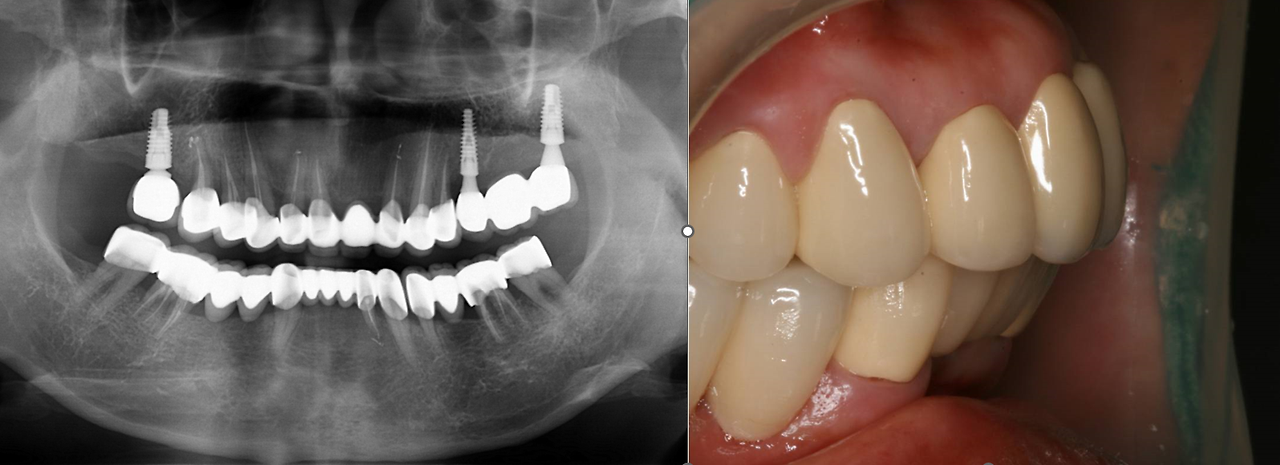

동요도가 너무 심해서 도저히 사용할 수 없는 상악의 구치부 보철물과 하악의 전치부와 소구치를 제외한 나머지 치아는 치주 보철로 계획하고 자연치로 연결할 수 없는 상악의 구치부는 최소한의 임플란트로 뽑은 자리를 대체하기로 했습니다. 위 증례를 치주 보철과 최소의 임플란트로 대체한 치료는 아래와 같습니다. 현재 10여 년 가까이 별문제 없이 사용하고 계십니다.

20220821_212938.png

이러한 치주 보철의 장점은 동요도가 많던 치아들이 서로 묶여서 강한 힘을 발휘할 수 있다는 것 말고도 심미적으로 많은 개선이 이루어집니다. 즉 뻐드러진 치아가 가지런해지고 돌출되었던 치아들도 정상적인 위치로 회복이 되지요.